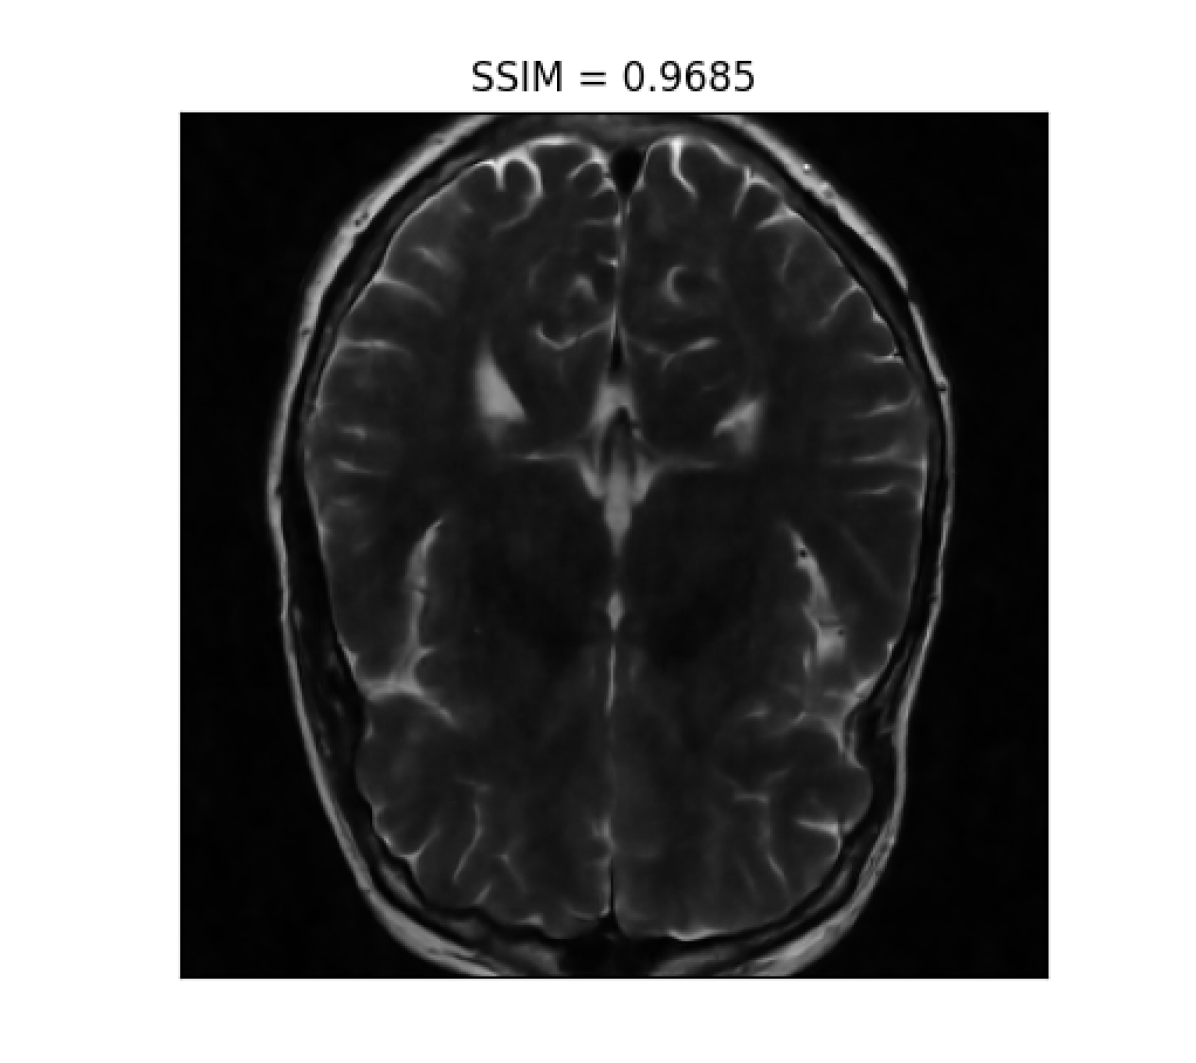

III-B2 Qualitative results

For visual inspection, we present the results of image reconstruction from data undersampled using SPARKLING trajectories generated for various target densities in Fig. 3 (T1subscriptT1\text{T}_{1}-w images) and Fig. 4 (T2subscriptT2\text{T}_{2}-w images). For the sake of space, we only report the best reconstruction results, i.e. with NC-PDNet. For T1subscriptT1\text{T}_{1}-weighted contrast, we show that all methods give similarly performing results, however 𝝆vdssubscript𝝆𝑣𝑑𝑠\boldsymbol{\rm\rho}_{vds} and 𝝆lbsubscript𝝆𝑙𝑏\boldsymbol{\rm\rho}_{lb} provide the best SSIM scores. Further, we observe that in this case, 𝝆vdssubscript𝝆𝑣𝑑𝑠\boldsymbol{\rm\rho}_{vds} is slightly better than 𝝆lbsubscript𝝆𝑙𝑏\boldsymbol{\rm\rho}_{lb}. On the contrary, for T2subscriptT2\text{T}_{2}-w contrast, 𝝆lbsubscript𝝆𝑙𝑏\boldsymbol{\rm\rho}_{lb} outperforms the other densities as reflected both visually in Fig. 4 and quantitatively (see Fig. 2).

Reference T2subscript𝑇2T_{2}-w Image (i) 𝝆vdssubscript𝝆𝑣𝑑𝑠\boldsymbol{\rm\rho}_{vds} (ii) 𝝆sbsubscript𝝆𝑠𝑏\boldsymbol{\rm\rho}_{sb} (iii) 𝝆lsbsubscript𝝆𝑙𝑠𝑏\boldsymbol{\rm\rho}_{lsb} (iii) 𝝆lbsubscript𝝆𝑙𝑏\boldsymbol{\rm\rho}_{lb}

Refer to caption Refer to caption Refer to caption Refer to caption Refer to caption

Figure 4: NC-PDNet-based image reconstruction for retrospective T2𝑇2T2-w imaging with slice 555 in file_brain_AXT2_200_2000019.h5 from validation data in fastMRI dataset for different target sampling densities.